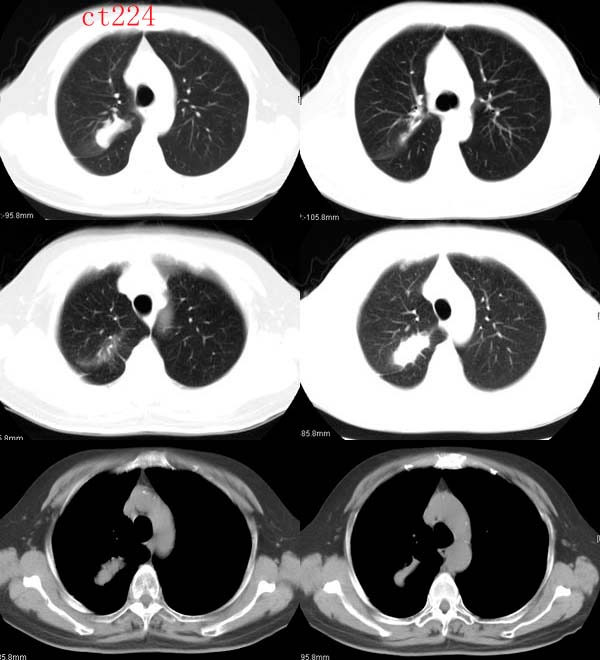

ct2240 mzjctmr提供 病理结果为高分化腺癌并支气管淋巴转移

女性,60岁,夜间发热一周余就诊。体温38度,血沉35mm/h

http://www.radida.com/radinet/read.php?tid=8574